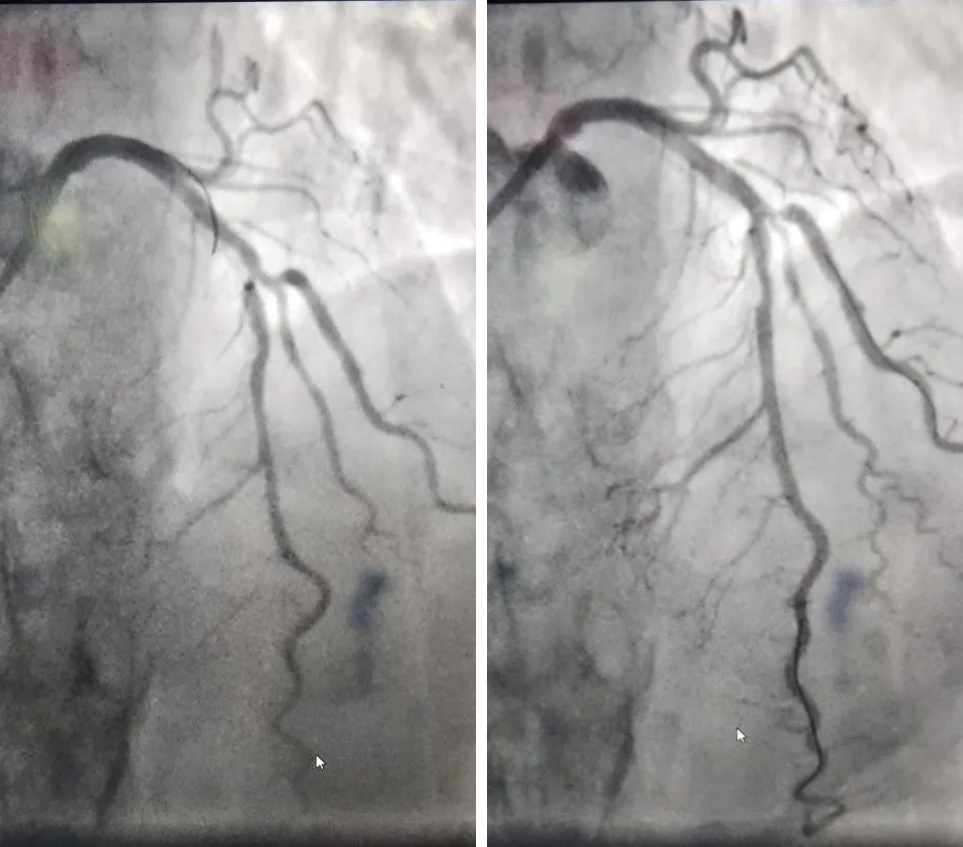

▲术前(左)术后(右)对比

患者李大娘(化名)年事已高,因间断胸闷20天,加重1周入院。冠状动脉造影显示,冠状动脉分支LAD近段重度狭窄,伴迂曲、成角、钙化病变,狭窄约85%,对角支开口90%狭窄。